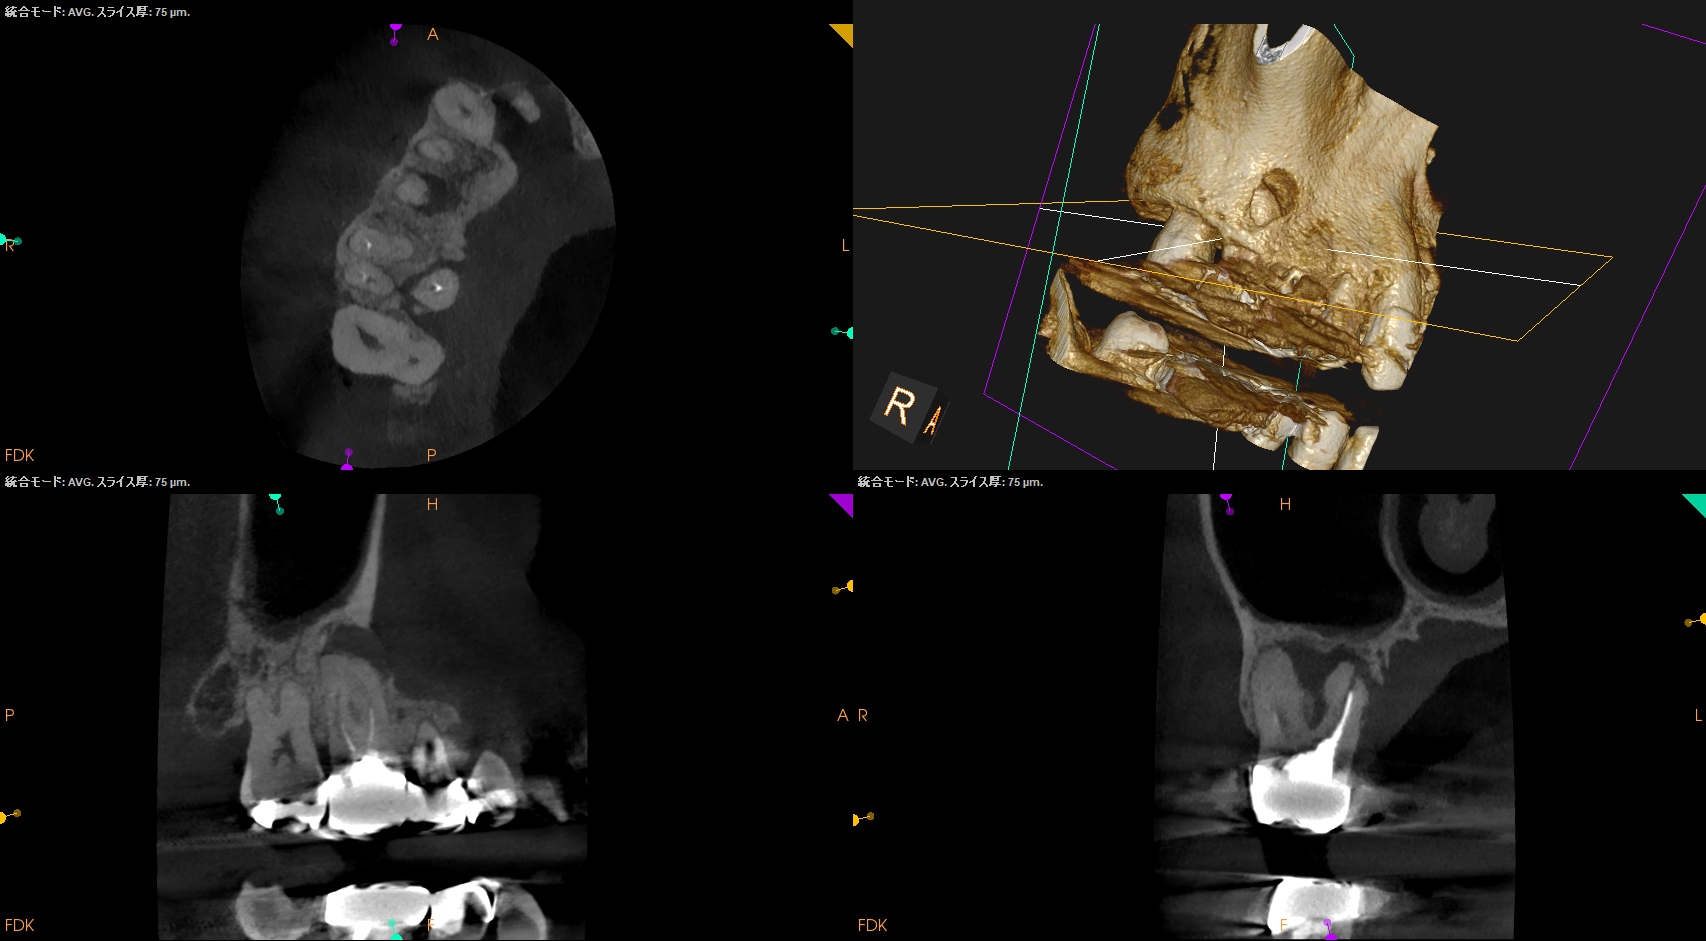

術後にPA, CBCTを撮影した。

#60.04で問題はなかった。

このように現代の歯内療法は、

Gutta Percha Pointの試適との戦い

であるということがわかるだろう。

問題はない。

ということでこの歯の予後は6ヶ月後にCheckする。